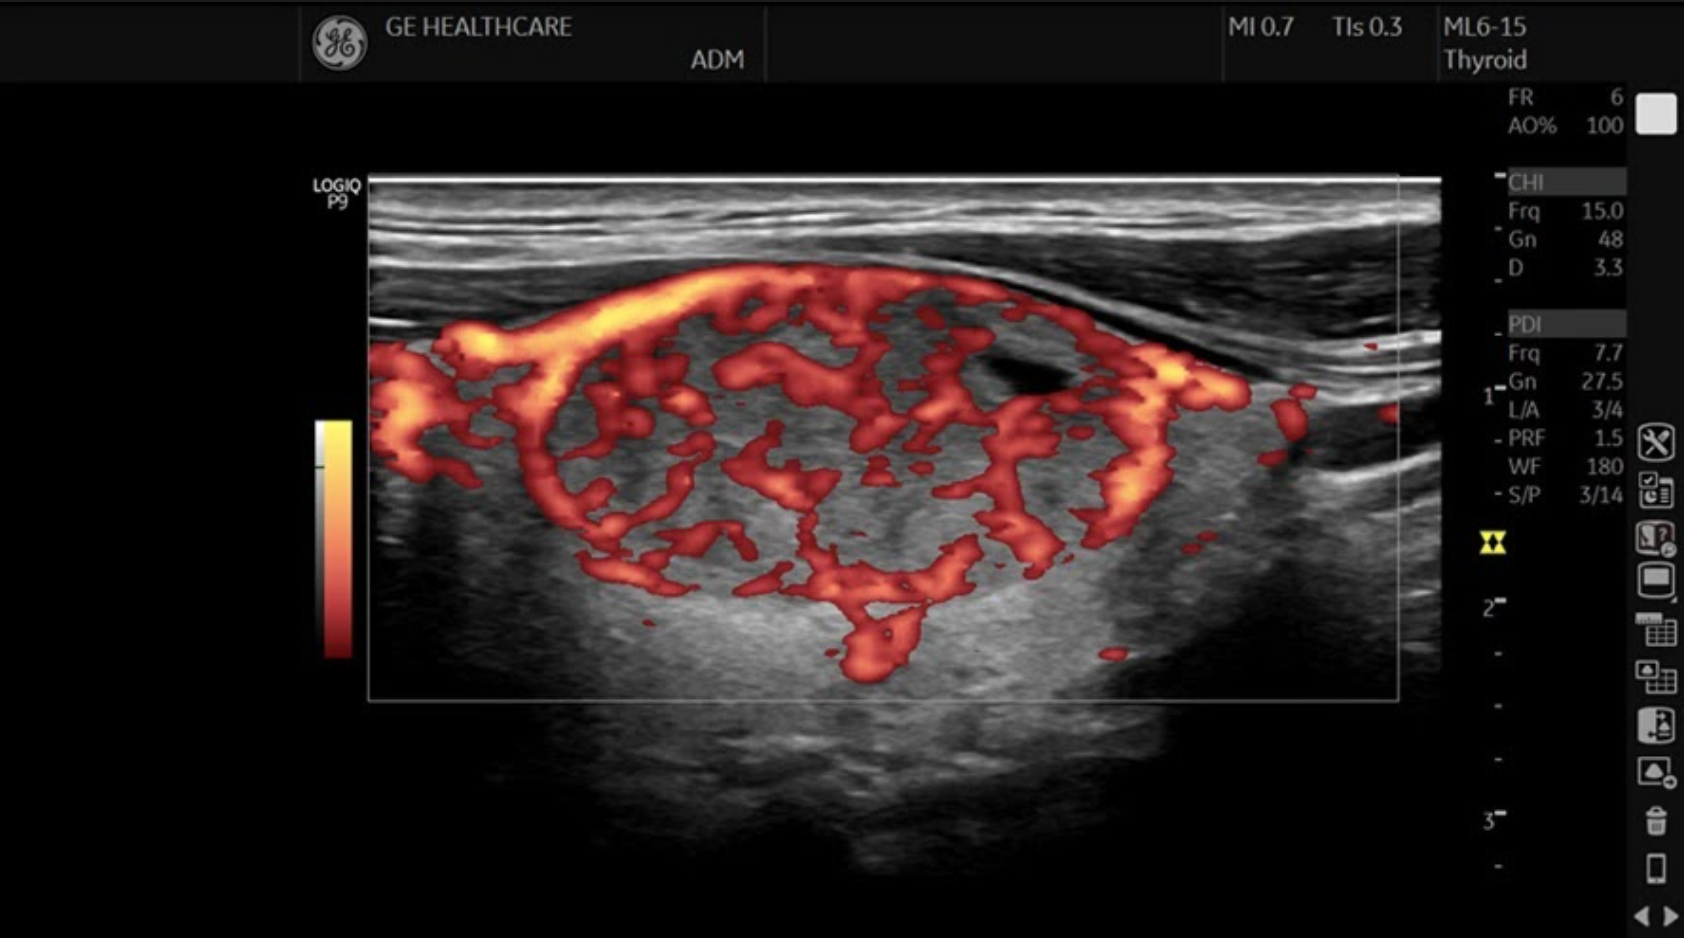

• Thyroid